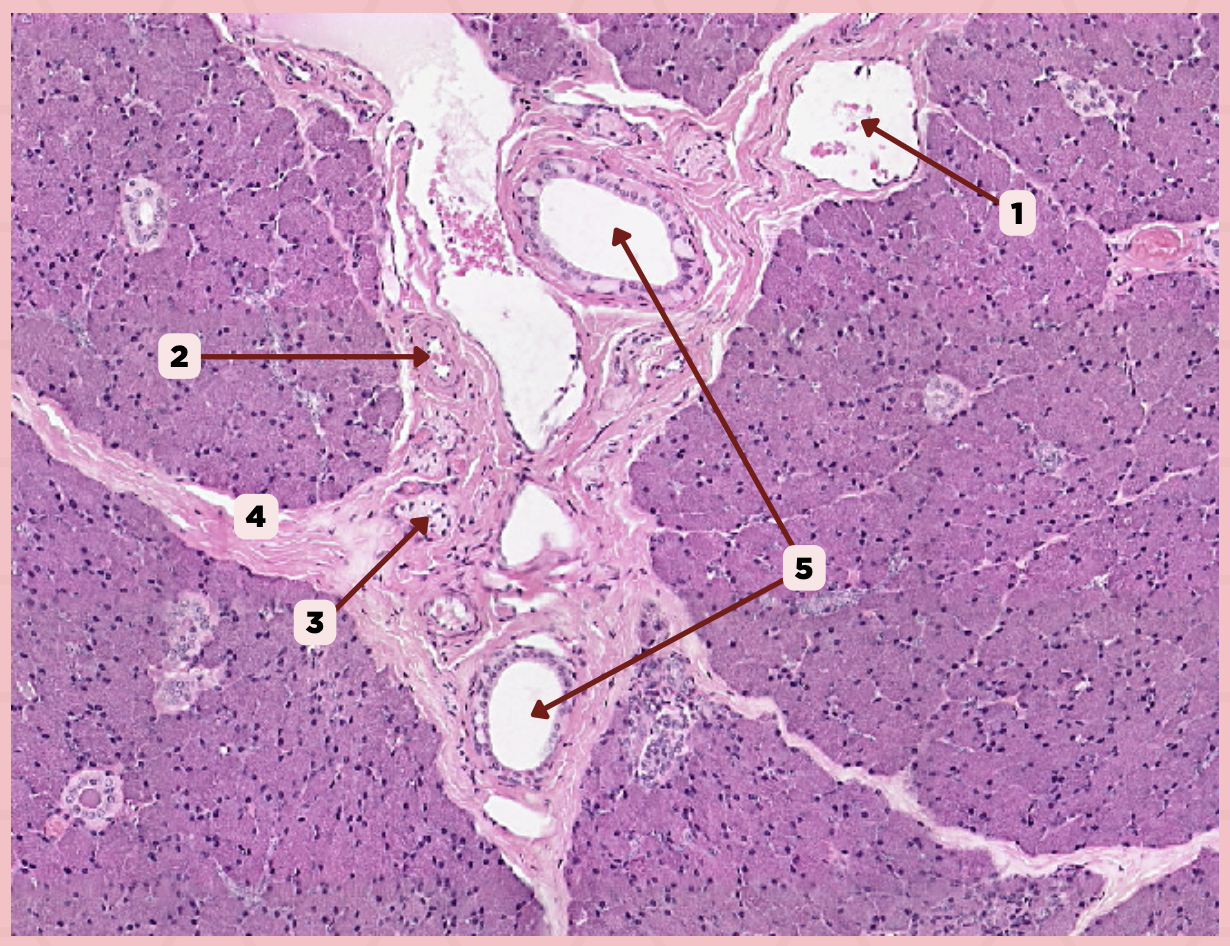

Parotid

Vein

Identify the structure labeled as 1.

Artery

Identify the structure labeled as 2.

Nerve

Identify the structure labeled as 3.

Interlobular Septa

Identify the structure labeled as 4.

Interlobular Duct

Identify the structure labeled as 5.